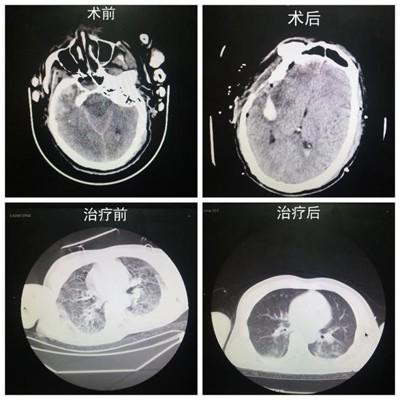

入院后经CT检查,患者的双侧额叶、右侧颞叶脑部挫裂伤、右侧额、颞部硬膜下形成血肿同时蛛网膜下腔出血。左侧颞骨及顶骨骨折并皮下软组织肿胀伴血肿、积气形成;左侧筛窦、上颌窦及双侧蝶窦积液;右侧肩胛骨粉碎性骨折;双肺间质性改变、双肺多发纤维索条灶;左侧胫骨撕脱性骨折,左侧腓骨远端及左侧距骨粉碎性骨折,左侧踝关节脱位,左足及小腿软组织多发积气。

急诊与重症医学科值班医生迅速组织人员投入抢救,立即给予深静脉置管,留置导尿。经神经外科医生共同会诊后,以“硬膜下血肿”收住入院。因为患者仍处于昏迷、休克状态,生命极度垂危,邢日强医生给予患者行气管插管,神经外科廖响辉主任进行“开颅右侧额颞部硬膜下血肿清除术+去骨瓣减压术+颅内压监测植入术”,及双下肢固定、清创缝合术。两小时之后,手术终于顺利完成,术后患者生命体征平稳。

手术后,急诊与重症医学科付伟主任查房后指示患者立即送入重症监护,进行镇痛镇静、脱水降颅压、抗感染、补液抗休克、维持水电解质酸碱平衡、对症支持等治疗,神经外科专科换药,动态复查相关指标,密切监测患者的生命体征。为了预防导管相关性感染,主管医生给予拔除右颈内置管,静疗小组行右上肢中线导管置管。患者生命体征平稳之后,顺利脱机拔管,并转入急诊病区进行康复治疗。